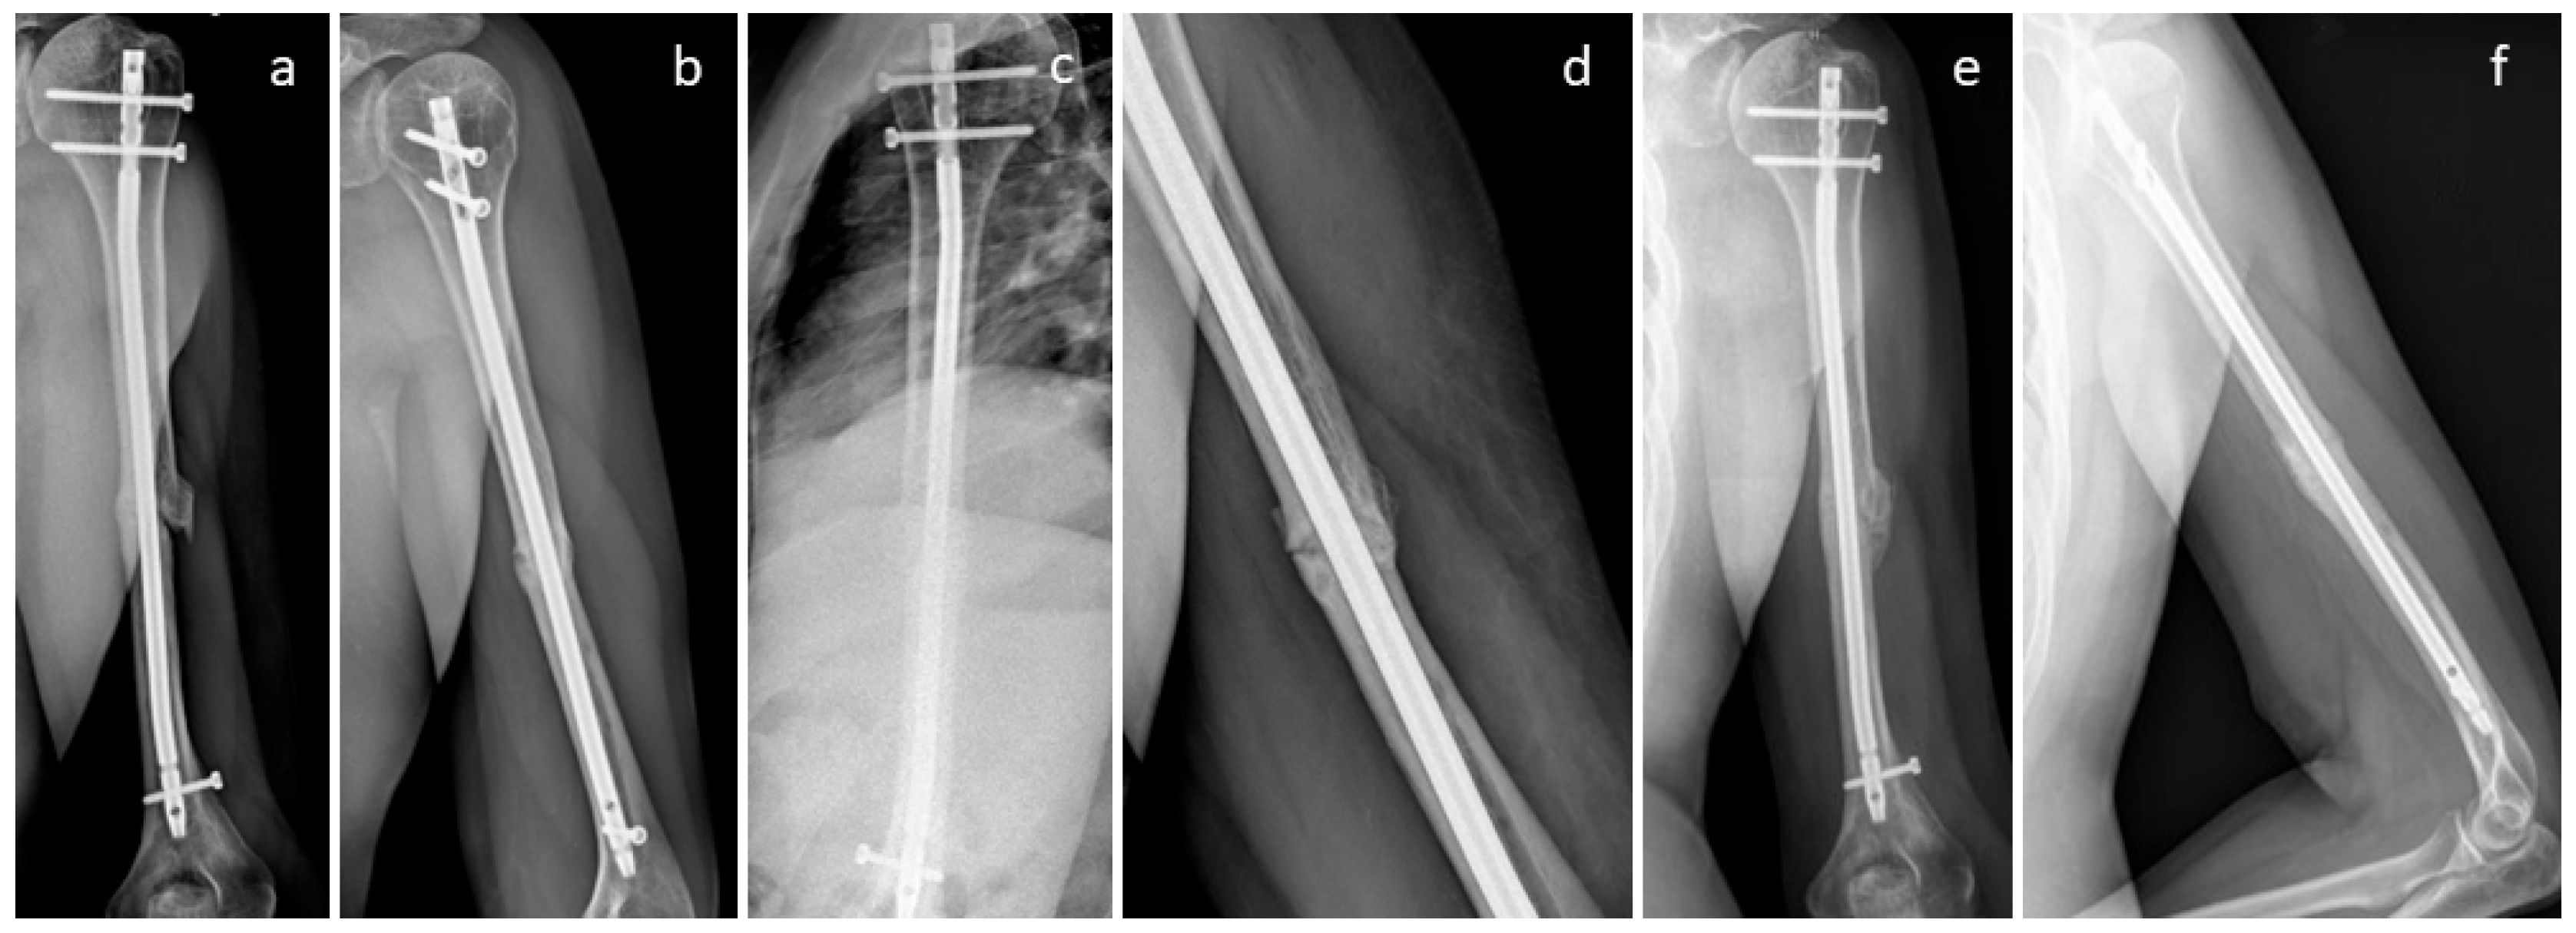

3.4. Selected Case Descriptions